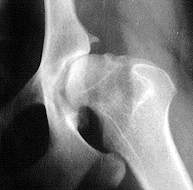

schlechte Hüfte